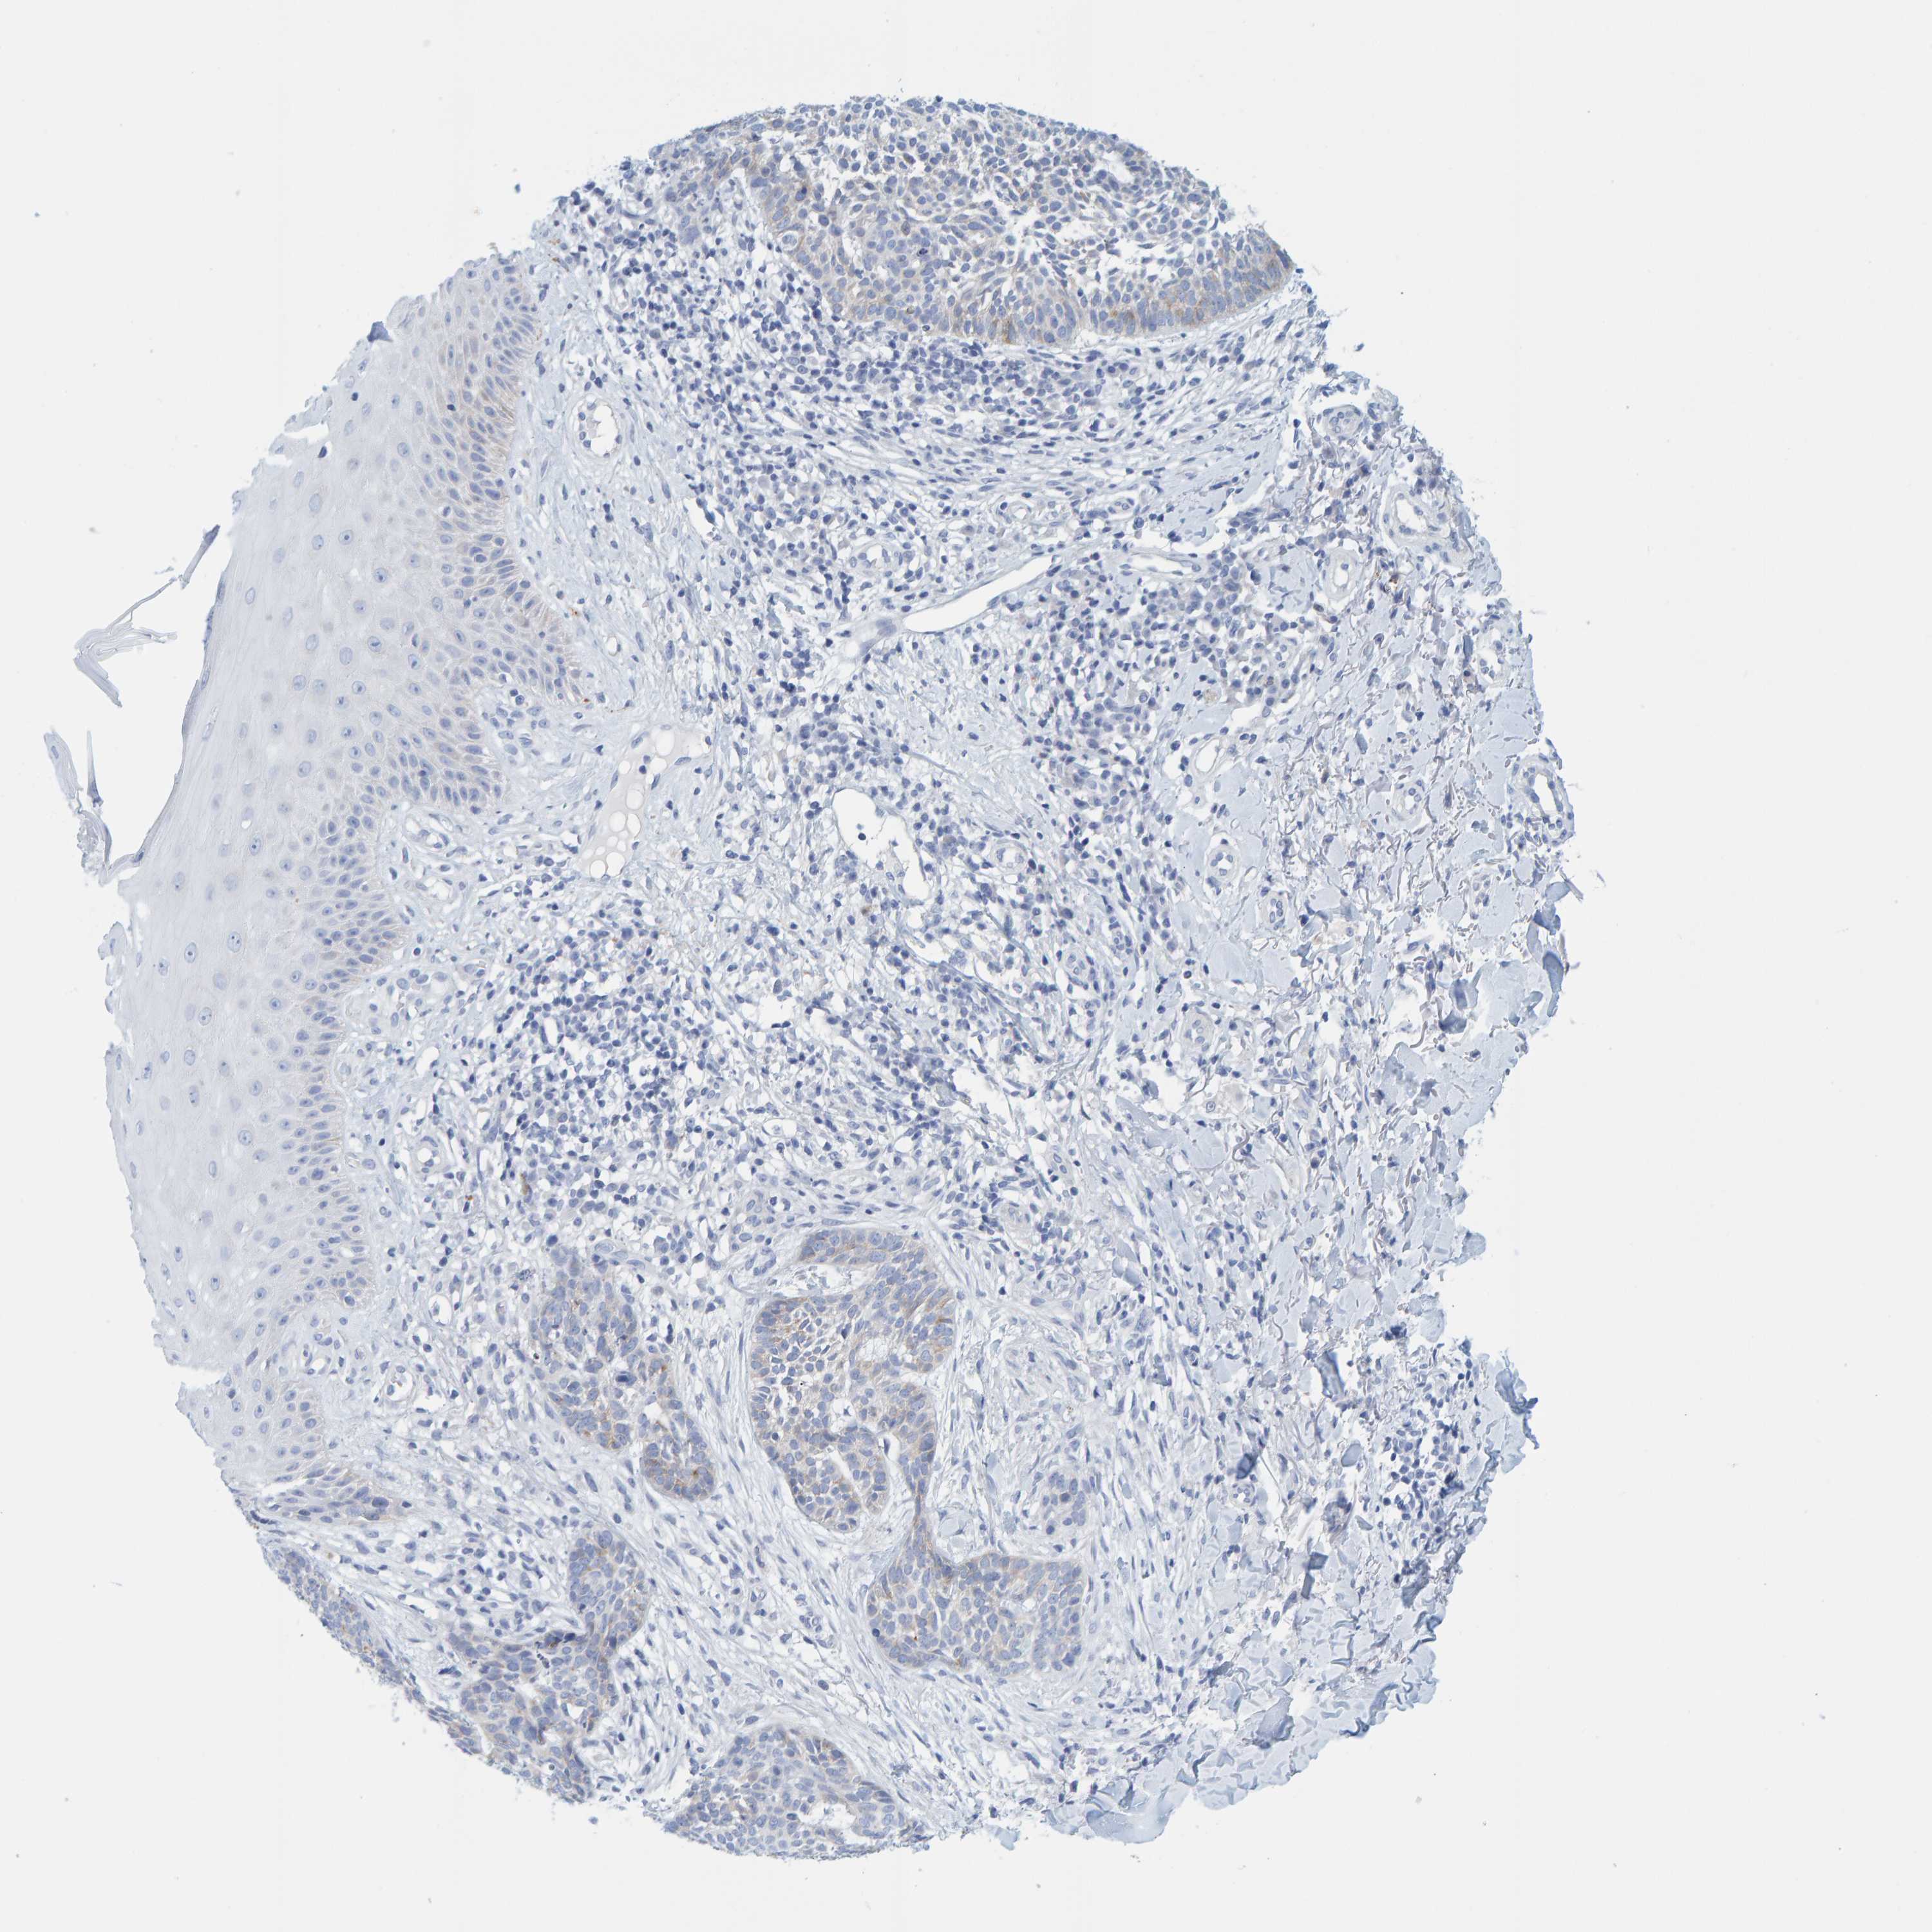

SKIN CANCER - Protein expressioni

A mouse-over function shows sample information and annotation data. Click on an image to view it in a full screen mode. Samples can be filtered based on level of antibody staining by selecting one or several of the following categories: high, medium, low and not detected. The assay and annotation is described here.

Antibody stainingi

Antibody staining in the annotated cell types in the current human tissue is reported as not detected, low, medium, or high, based on conventional immunohistochemistry profiling in selected tissues. This score is based on the combination of the staining intensity and fraction of stained cells.

Each image is clickable and will lead to virtual microscopy that enables deeper exploration of all samples and also displays staining intensity scores, fraction scores and subcellular localization as well as patient and tissue information for each sample.

Antibody HPA023021

Basal cell carcinoma

Squamous cell carcinoma, NOS